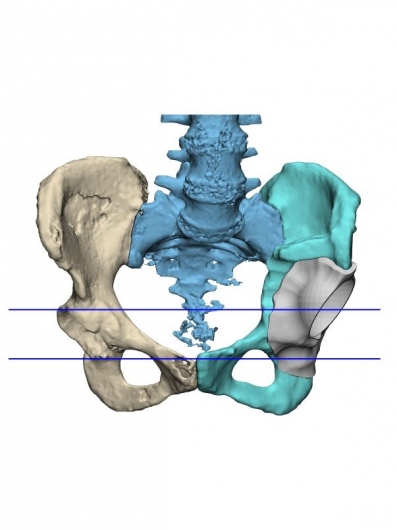

Practico una ortopedia centrada en usted como paciente, moderna, mínimamente invasiva y basada en evidencia científica. Me mantengo en constante actualización nacional e internacional y estoy certificado en cirugía de reemplazo articular con asistencia robótica con el sistema Mako® de Stryker, una tecnología de última generación para el reemplazo de cadera y rodilla, la más avanzada de Latinoamérica y el mundo.

Gracias a la planificación quirúrgica en modelos tridimensionales personalizados, este sistema permite una precisión milimétrica, lo que se traduce en: